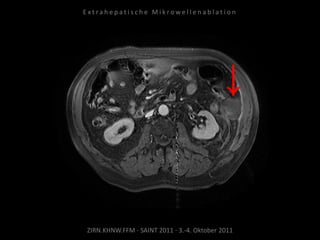

Situation:

Metastasierung über längeren Zeitraum

lokal begrenzt,

1 Metastase progredient.

Organnahe Lage in unmittelbarer

Nachbarschaft zur linken Niere bzw. zum

Colon descendens.

Ablation am 17.08.2010

Metastase lateral der linken Niere:

1 Nadelposition.

Metastase medial des linken

Musculus iliacus: